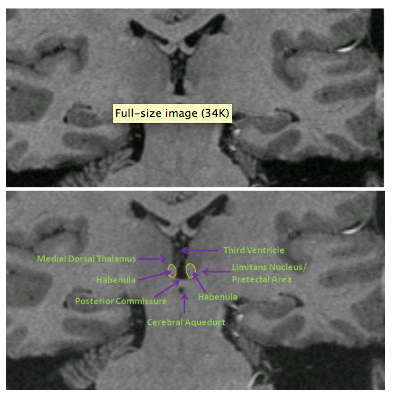

habenula1